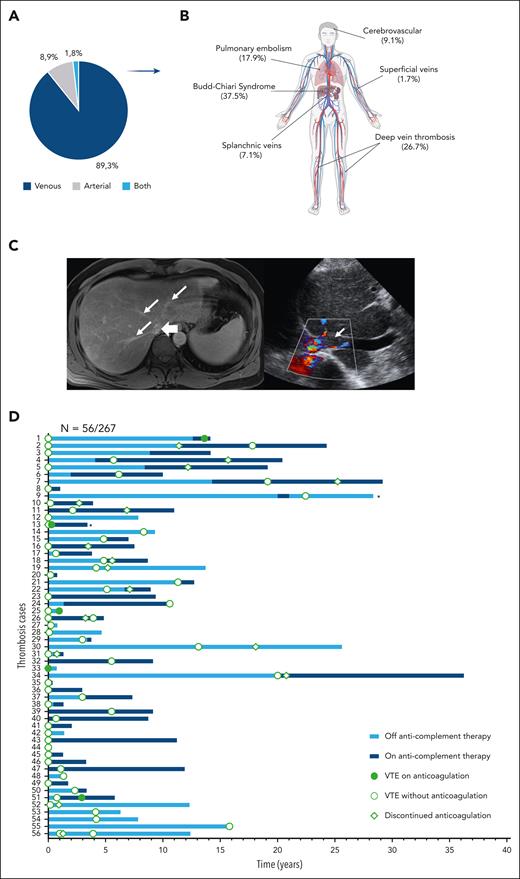

Most TEs originated in the venous system (89.3%) whereas 8.9% of the cases involved the cerebrovascular arteries, and 1.8% affected both arterial and venous compartments. Remarkably, TEs occurred in unusual sites in the majority of cases, with Budd-Chiari syndrome as the most frequent (37.5%), followed by deep vein thrombosis (DVT, 26.7%), DVT complicated by pulmonary embolism (17.9%), cerebrovascular (9.1%), splanchnic (7.1%), and superficial veins (1.7%, Figure 1).

Features of Budd-Chiari syndrome in PNH. (A) A pie chart illustrates the type of TEs. (B) A cartoon showcases the anatomic site of origin of thromboses. (C) Left panel shows magnetic resonance imaging (MRI) of a 59-year-old man, whereby on the axial postcontrast VIBE (volumetric interpolated breath-hold examination), the hepatic veins are decreased in caliber (thin arrows) and demonstrate peripheral pruning, however there is no residual hepatic venous filling defect to suggest thrombus. The intrahepatic inferior vena cava (IVC; thick arrow) is significantly narrowed without IVC thrombosis. On the right, a Doppler ultrasound image of the IVC of an 89-year-old male shows the hypoechoic and nonocclusive thrombus in the lumen (arrow). (D) A swimmer plot illustrates the longitudinal follow-up, and anticomplement and anticoagulation strategies in patients experiencing TEs in our cohort. ∗Patients for whom precise dates on subsequent thrombotic events (5 episodes for UPN 9 and 3 episodes for UPN 13) are lacking.